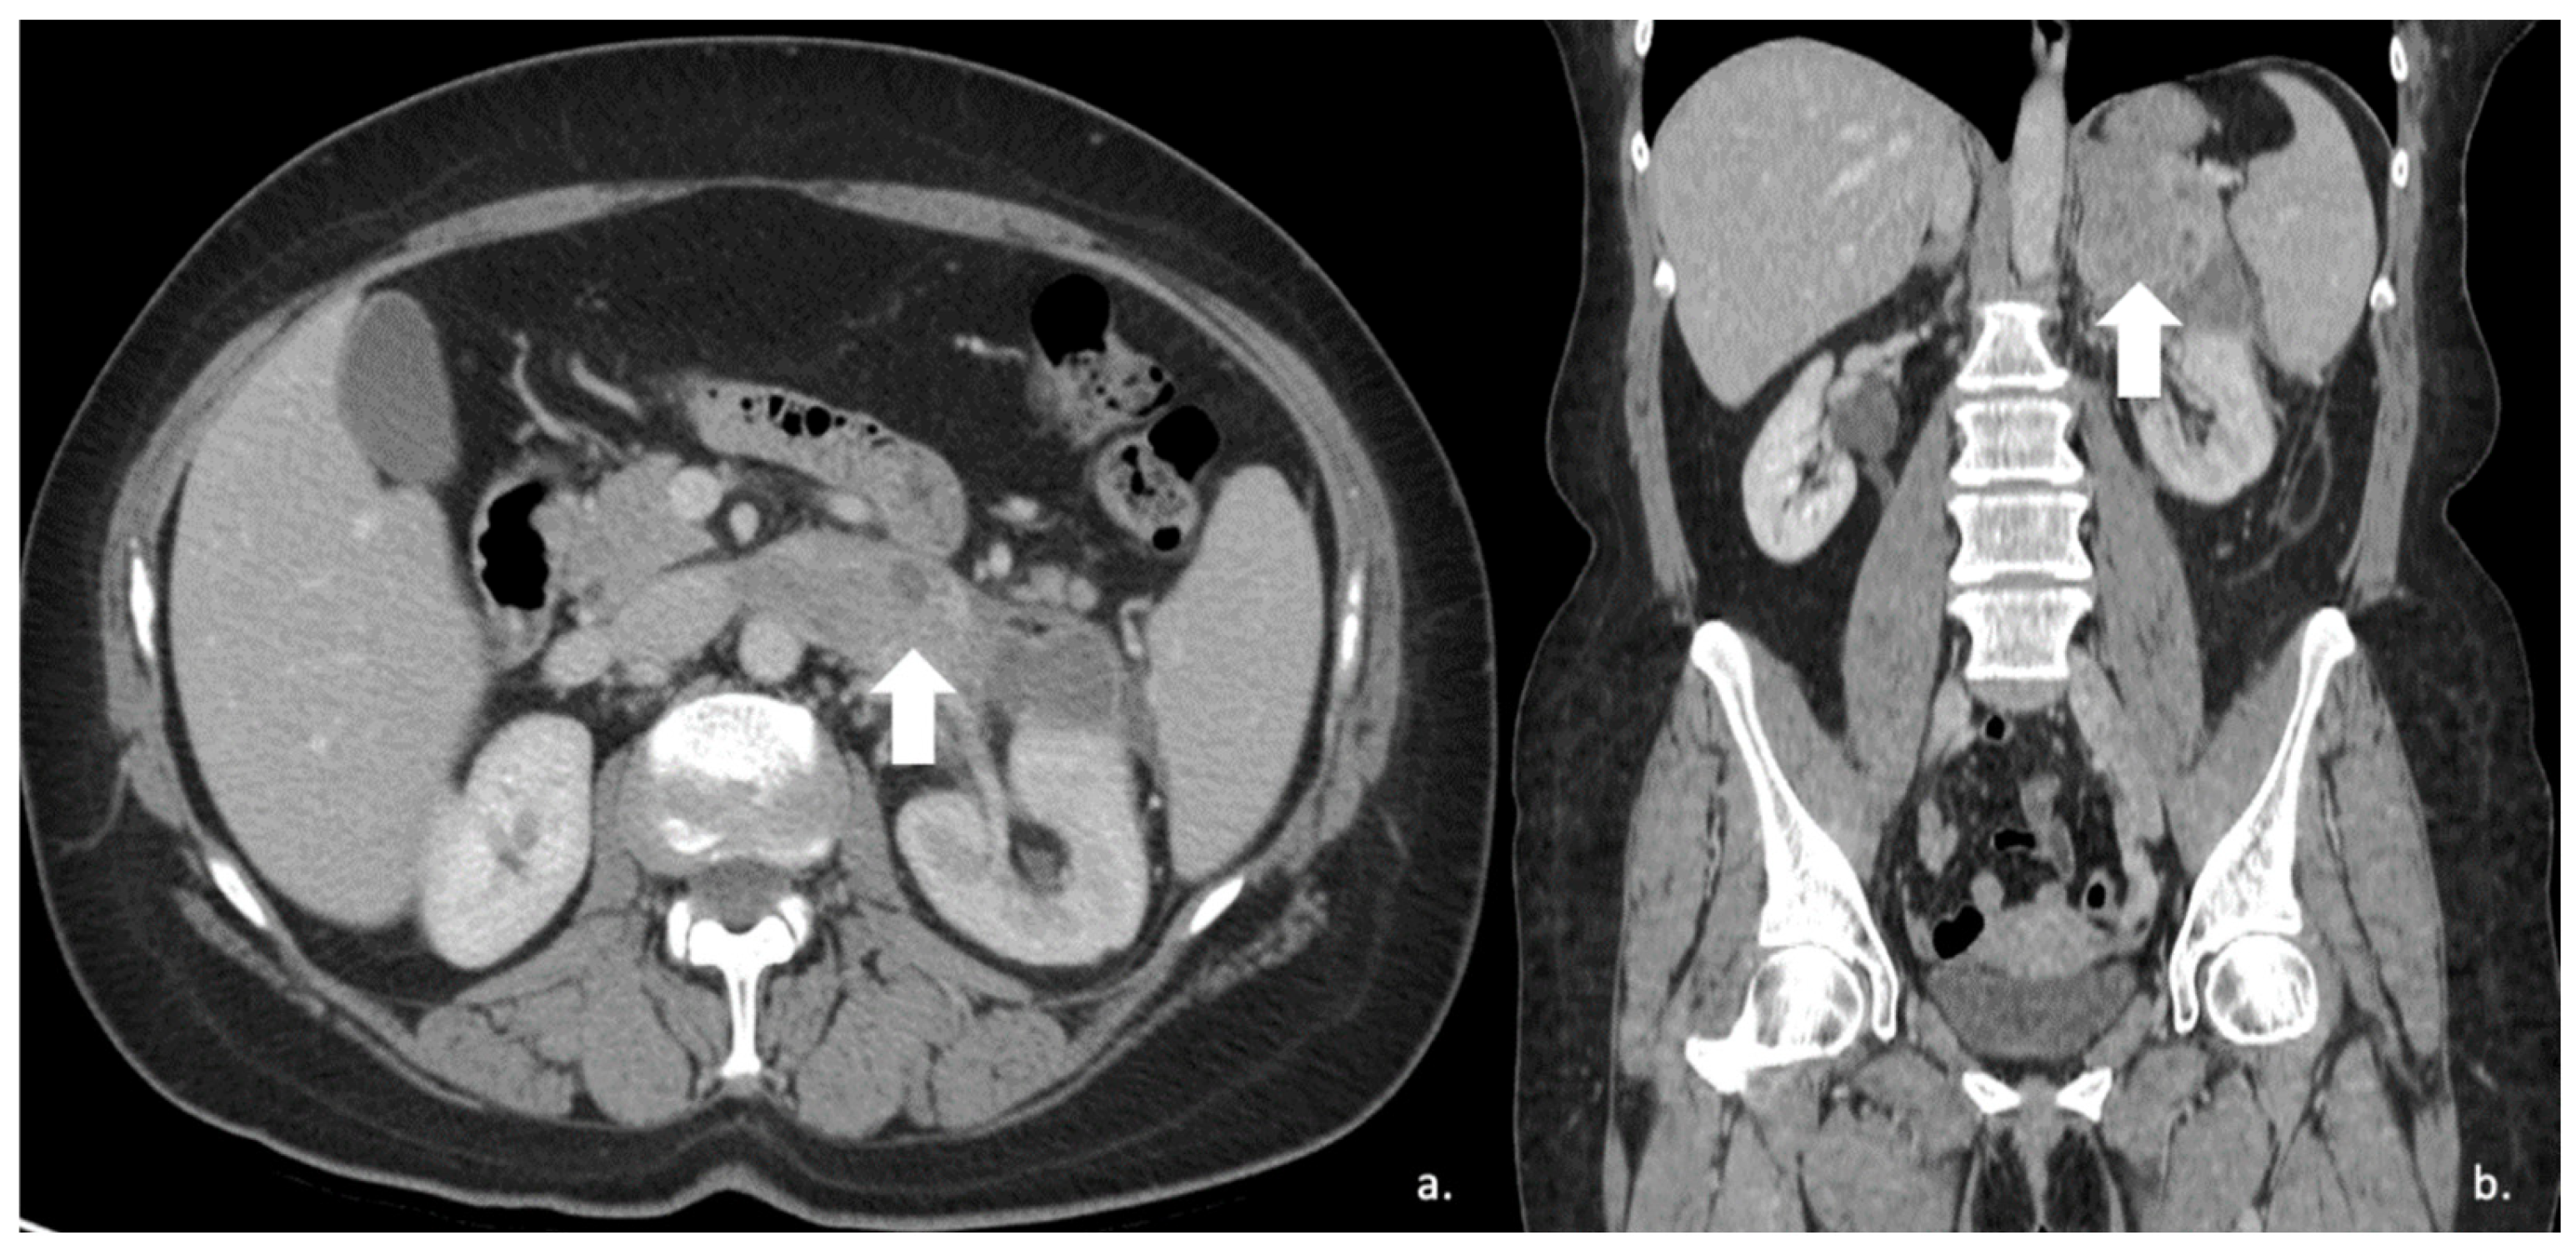

Figure 4.

36-year-old man with history of night sweats, hypertension, and tachycardia due to pheochromocytoma (arrow). Non-contrast CT shows an inhomogeneous right adrenal mass > 20 HU (A). In the arterial phase (B), the mass shows intense enhancement of the solid components with persistent enhancement. In the late phase (C), absolute contrast medium washout is <50%.